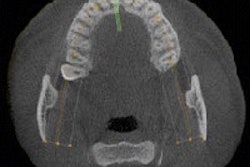

The KaVo Kerr Group Imaging has released Invivo 5.4, an upgrade to its cone-beam CT (CBCT) 3D imaging treatment and planning software.

The upgrade is integrated with Instrumentarium Dental, Gendex and Soredex 3D imaging systems, according to the company.

The new version of the treatment software is included with new Instrumentarium OP300 Maxio cone-beam 3D scanners, Gendex GXDP-700S system, and Soredex Cranex 3Dx and Scanora systems.